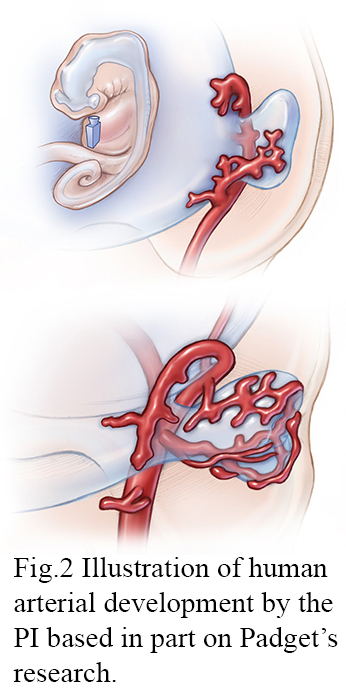

© JHU, Illustrated by Lydia Gregg based on art by Dorcas Hager Padget

Lydia is an Associate Professor with a joint appointment in the Departments of Radiology and Art as Applied to Medicine. Her funded project entitled, Communicating Comparative Embryonic Arterial Development: An Interactive 3D Educational Tool Depicting Zebrafish and Human Ocular Arteries, seeks to visualize the development of major intracranial and ocular arteries by creating a comparative 3D educational tool that integrates human serial section data and zebrafish confocal microscopy data (Fig. 1). Developing this dynamic visualization will build on Lydia’s prior neurovascular embryology work (Fig. 2) 1-4 and experience illustrating, animating, and researching neurovascular anatomy 5-8.